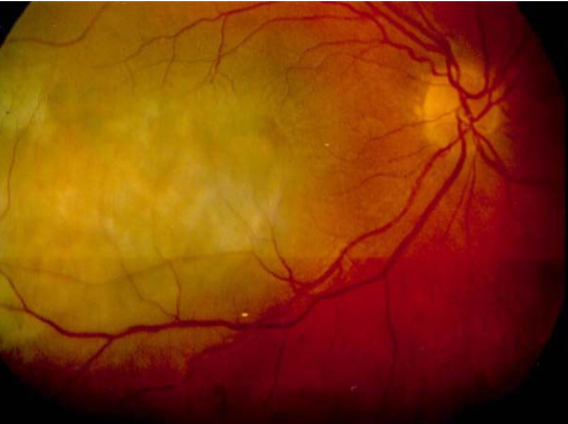

choroidal melanoma

melanoma

melanoma

melanoma

melanoma

melanoma

melanoma

melanoma

melanoma

melanoma

melanoma

melanoma

melanoma

melanoma

melanoma

melanoma

melanoma